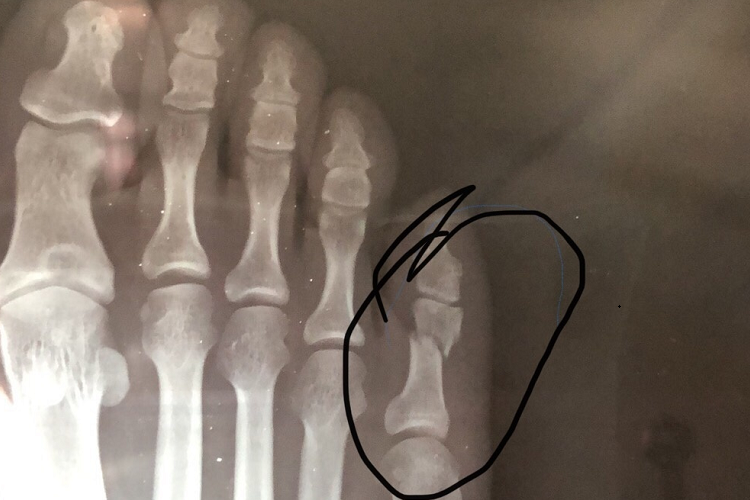

小脚趾第五趾骨折的愈合时间因人而异,受到多种因素的影响,一般在1-8个月,与骨折程度、个体身体状况、康复训练质量等方面有关,患者应在治疗过程中积极配合,以促进早日康复。

1、轻度骨折:如果骨折只是细微的裂缝,未发生明显移位,在受伤后能迅速采取恰当的治疗措施,如固定和休息,通常在4-6周左右,骨折处会开始愈合,经过2-3个月的时间能基本恢复正常。

2、中度骨折:骨折有一定程度的移位,但通过手法复位或外固定能够达到较好的位置。这种情况下,骨折愈合可能需要6-8周,之后还需要3-4个月的康复期来恢复脚趾的功能和力量。

3、严重骨折及复杂情况:如粉碎性骨折、合并周围软组织严重损伤或出现感染等并发症。骨折愈合可能需要8-12周甚至更久,完全恢复正常功能可能需要4-6个月,期间需要密切观察和针对性治疗。